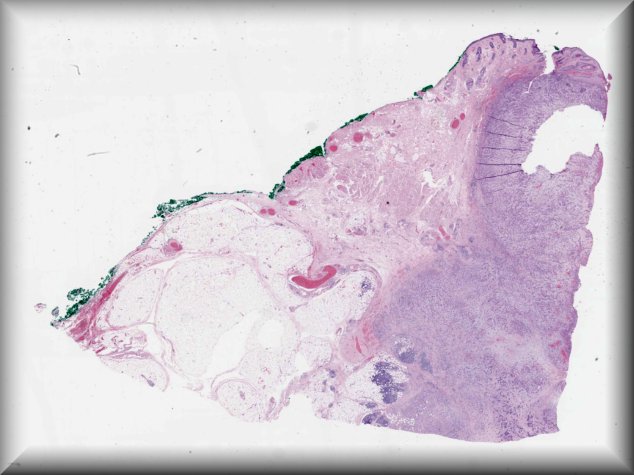

Nora Laver (Boston): A 44-year-old male presented with right upper eyelid swelling of one month; he was treated for presumed pre-septal cellulitis with oral antibiotics without improvement. |